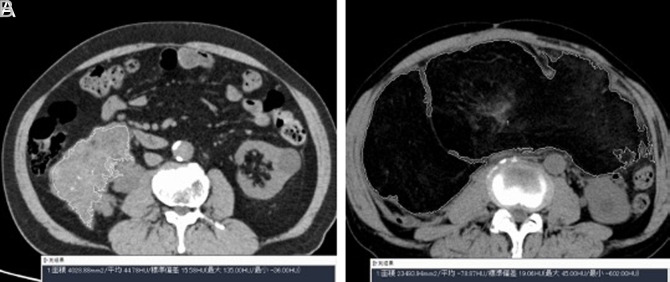

Objective: Liposarcoma (LPS) is classified into 4 subtypes. As some subtypes have a high recurrence rate, knowing the risk of recurrence before surgery is important. Here, we aimed to investigate the relationship between Hounsfield units (HU) derived from preoperative computed tomography (CT) and the prognosis of patients undergoing surgery.

Materials and methods: We included 32 patients who underwent surgery for LPS between 2014 and 2022. Preoperative plain CT images were collected, and the HU value of each LPS was measured. The association between 2 HU categories (HU < cut-off vs. ≥ cut-off) and clinical variables was assessed. The optimal cut-off value was determined using statistical methods. We used the Kaplan-Meier method to determine the differences between the 2 HU categories at 2 endpoints: recurrence-free survival (RFS) and overall survival (OS).

Results: The dedifferentiated subtype showed significantly higher HU values than the other subtypes (P < .001). The optimal cut-off value for HU was 20. HU < 20 was associated with young age, low-performance status, low Charlson Comorbidity Index, and well-differentiated pathology. The Kaplan-Meier curves demonstrated that RFS and OS were significantly shorter in patients with HU ≥ 20 than in those with HU < 20 (P = .007 and .04, respectively). However, when stratified based on subtype, no significant differences were observed between dedifferentiated and other subtypes.

Conclusion: HU ≥ 20 on preoperative CT was associated with poor prognosis in LPS patients. Our findings suggest that preoperative CT-derived HU values may serve as useful predictors of prognosis.